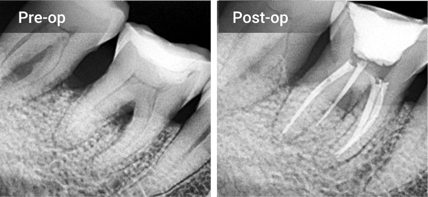

Excellent Radiopacity

The highly radiopaque and hydrophilic sealer provides tight

adhesion to both dentin and gutta percha points.

radiopacity@2x